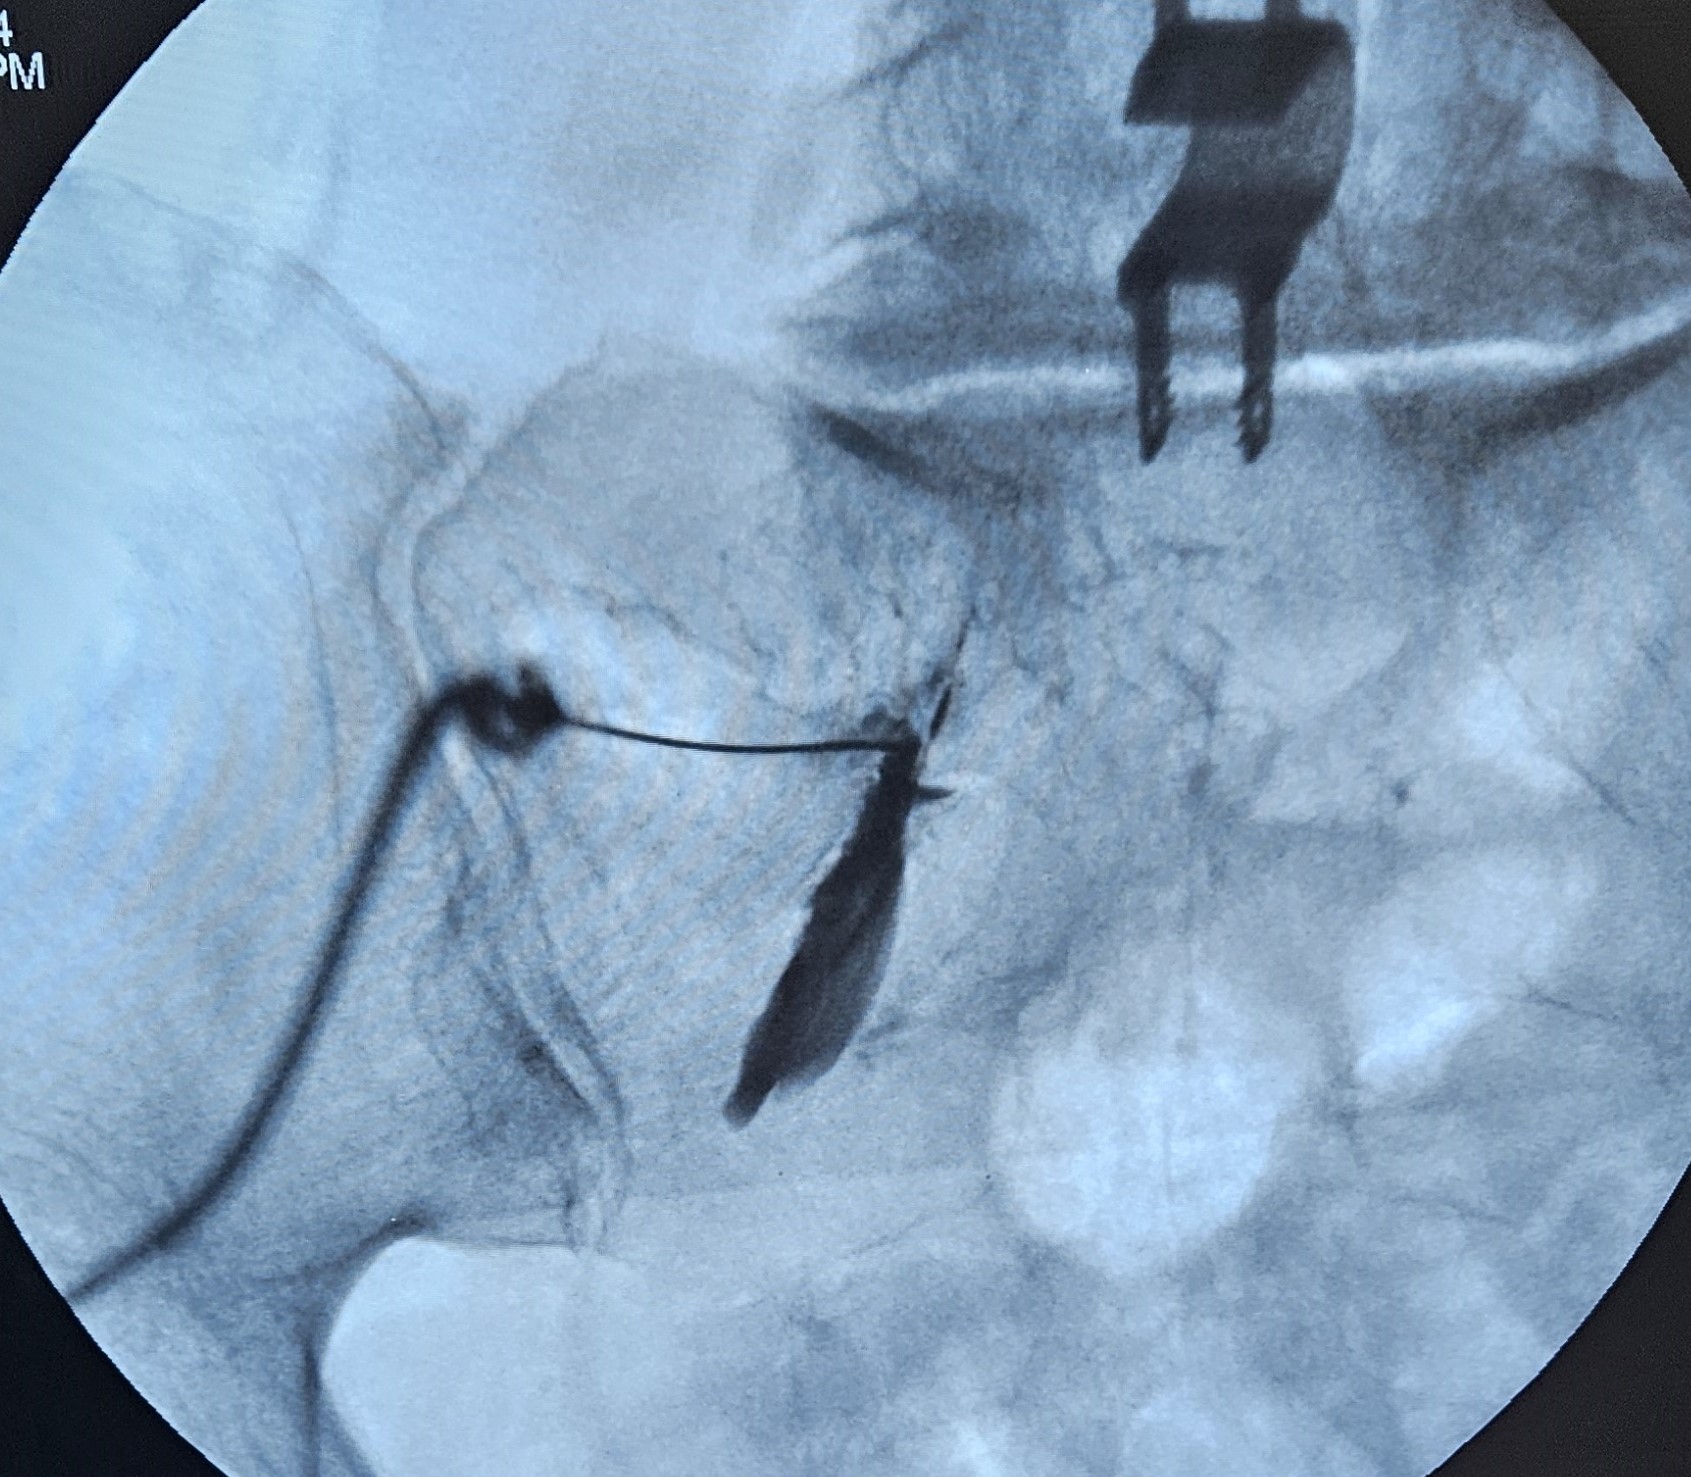

Πρόκειται για μια ελάχιστα επεμβατική πράξη, όπου μια ειδική βελόνα με ενσωματωμένο ηλεκτρόδιο εισάγεται στο σπονδυλικό τρήμα στο επίπεδο του ραχιαίου γαγγλίου της οπίσθιας ρίζας. με χρήση παλμικής ραδιοσυχνότητας γίνεται η διέγερση του γαγγλίου, με στόχο την τροποποίηση της μεταφοράς και αντίληψης των επώδυνων μηνυμάτων.

Πρόκειται για μια τεχνική απονεύρωσης των αρθρώσεων της σπονδυλικής στήλης μέσω κατάλυσης των μέσων νευρικών κλάδων που είναι υπεύθυνοι για τη νεύρωση κάθε άρθρωσης. Γίνεται μέσω εμφύτευσης ειδικών βελόνων με εμφυτευμένο ηλεκτρόδιο και χρήση κρύου ή θερμότητας για την καταστροφή των αισθητικών νευρικών κλάδων.

Η έγχυση αφορά στη χορήγηση διαλύματος τοπικού αναισθητικού και κορτιζόνης απευθείας στο κατώτερο τμήμα της ιερολαγονίου άρθρωσης υπό ακτινοσκοπική καθοδήγηση. Η απονεύρωση γίνεται με χρήση θερμοπηξίας ή κρυοπηξίας και στοχεύει στην κατάλυση των αισθητικών κλάδων που τροφοδοτούν την ιερολαγόνιο άρθρωση, οι οποίοι βρίσκονται παραπλεύρως κάθε ιερού τρήματος.